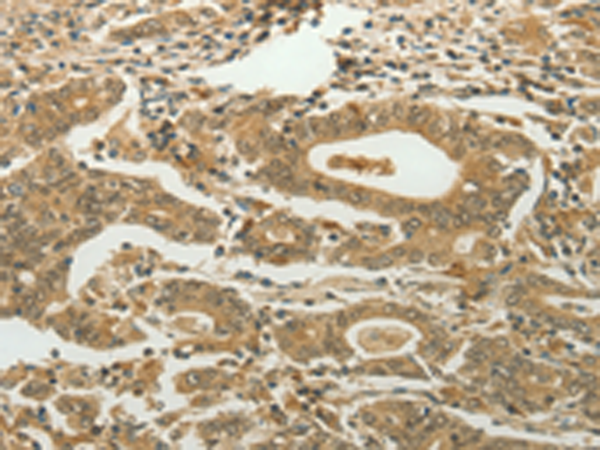

分类: 科研抗体货号: P11271别名: SMRT; TRAC; CTG26; SMRTE; TRAC1; N-CoR2; TNRC14; TRAC-1; SMAP270; SMRTE-tau应用: IHC反应种属: Human